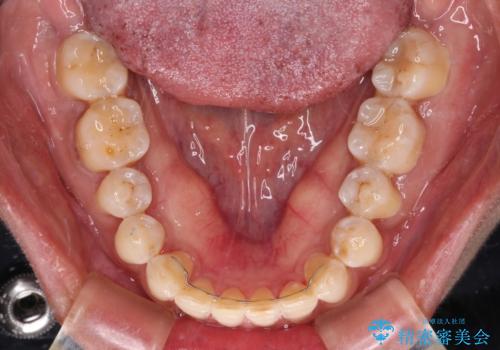

反対咬合の改善 途中で出産をしながらワイヤー矯正

- 矯正装置

- メタルブラケット

- 前歯の隙間と反対咬合を気にして来院された患者様です。

マウスピース矯正も提案しましたが、しっかりと使用する自信がないとのことで、ワイヤー装置により矯正治療を行うこととしました。

咬合力が強く、反対咬合の改善に時間がかかりましたが、その後はスムーズに進めることができました。

途中、妊娠と出産があり、治療が中断したため、治療期間は延びましたが、出産も矯正治療も無事に終えることができました。